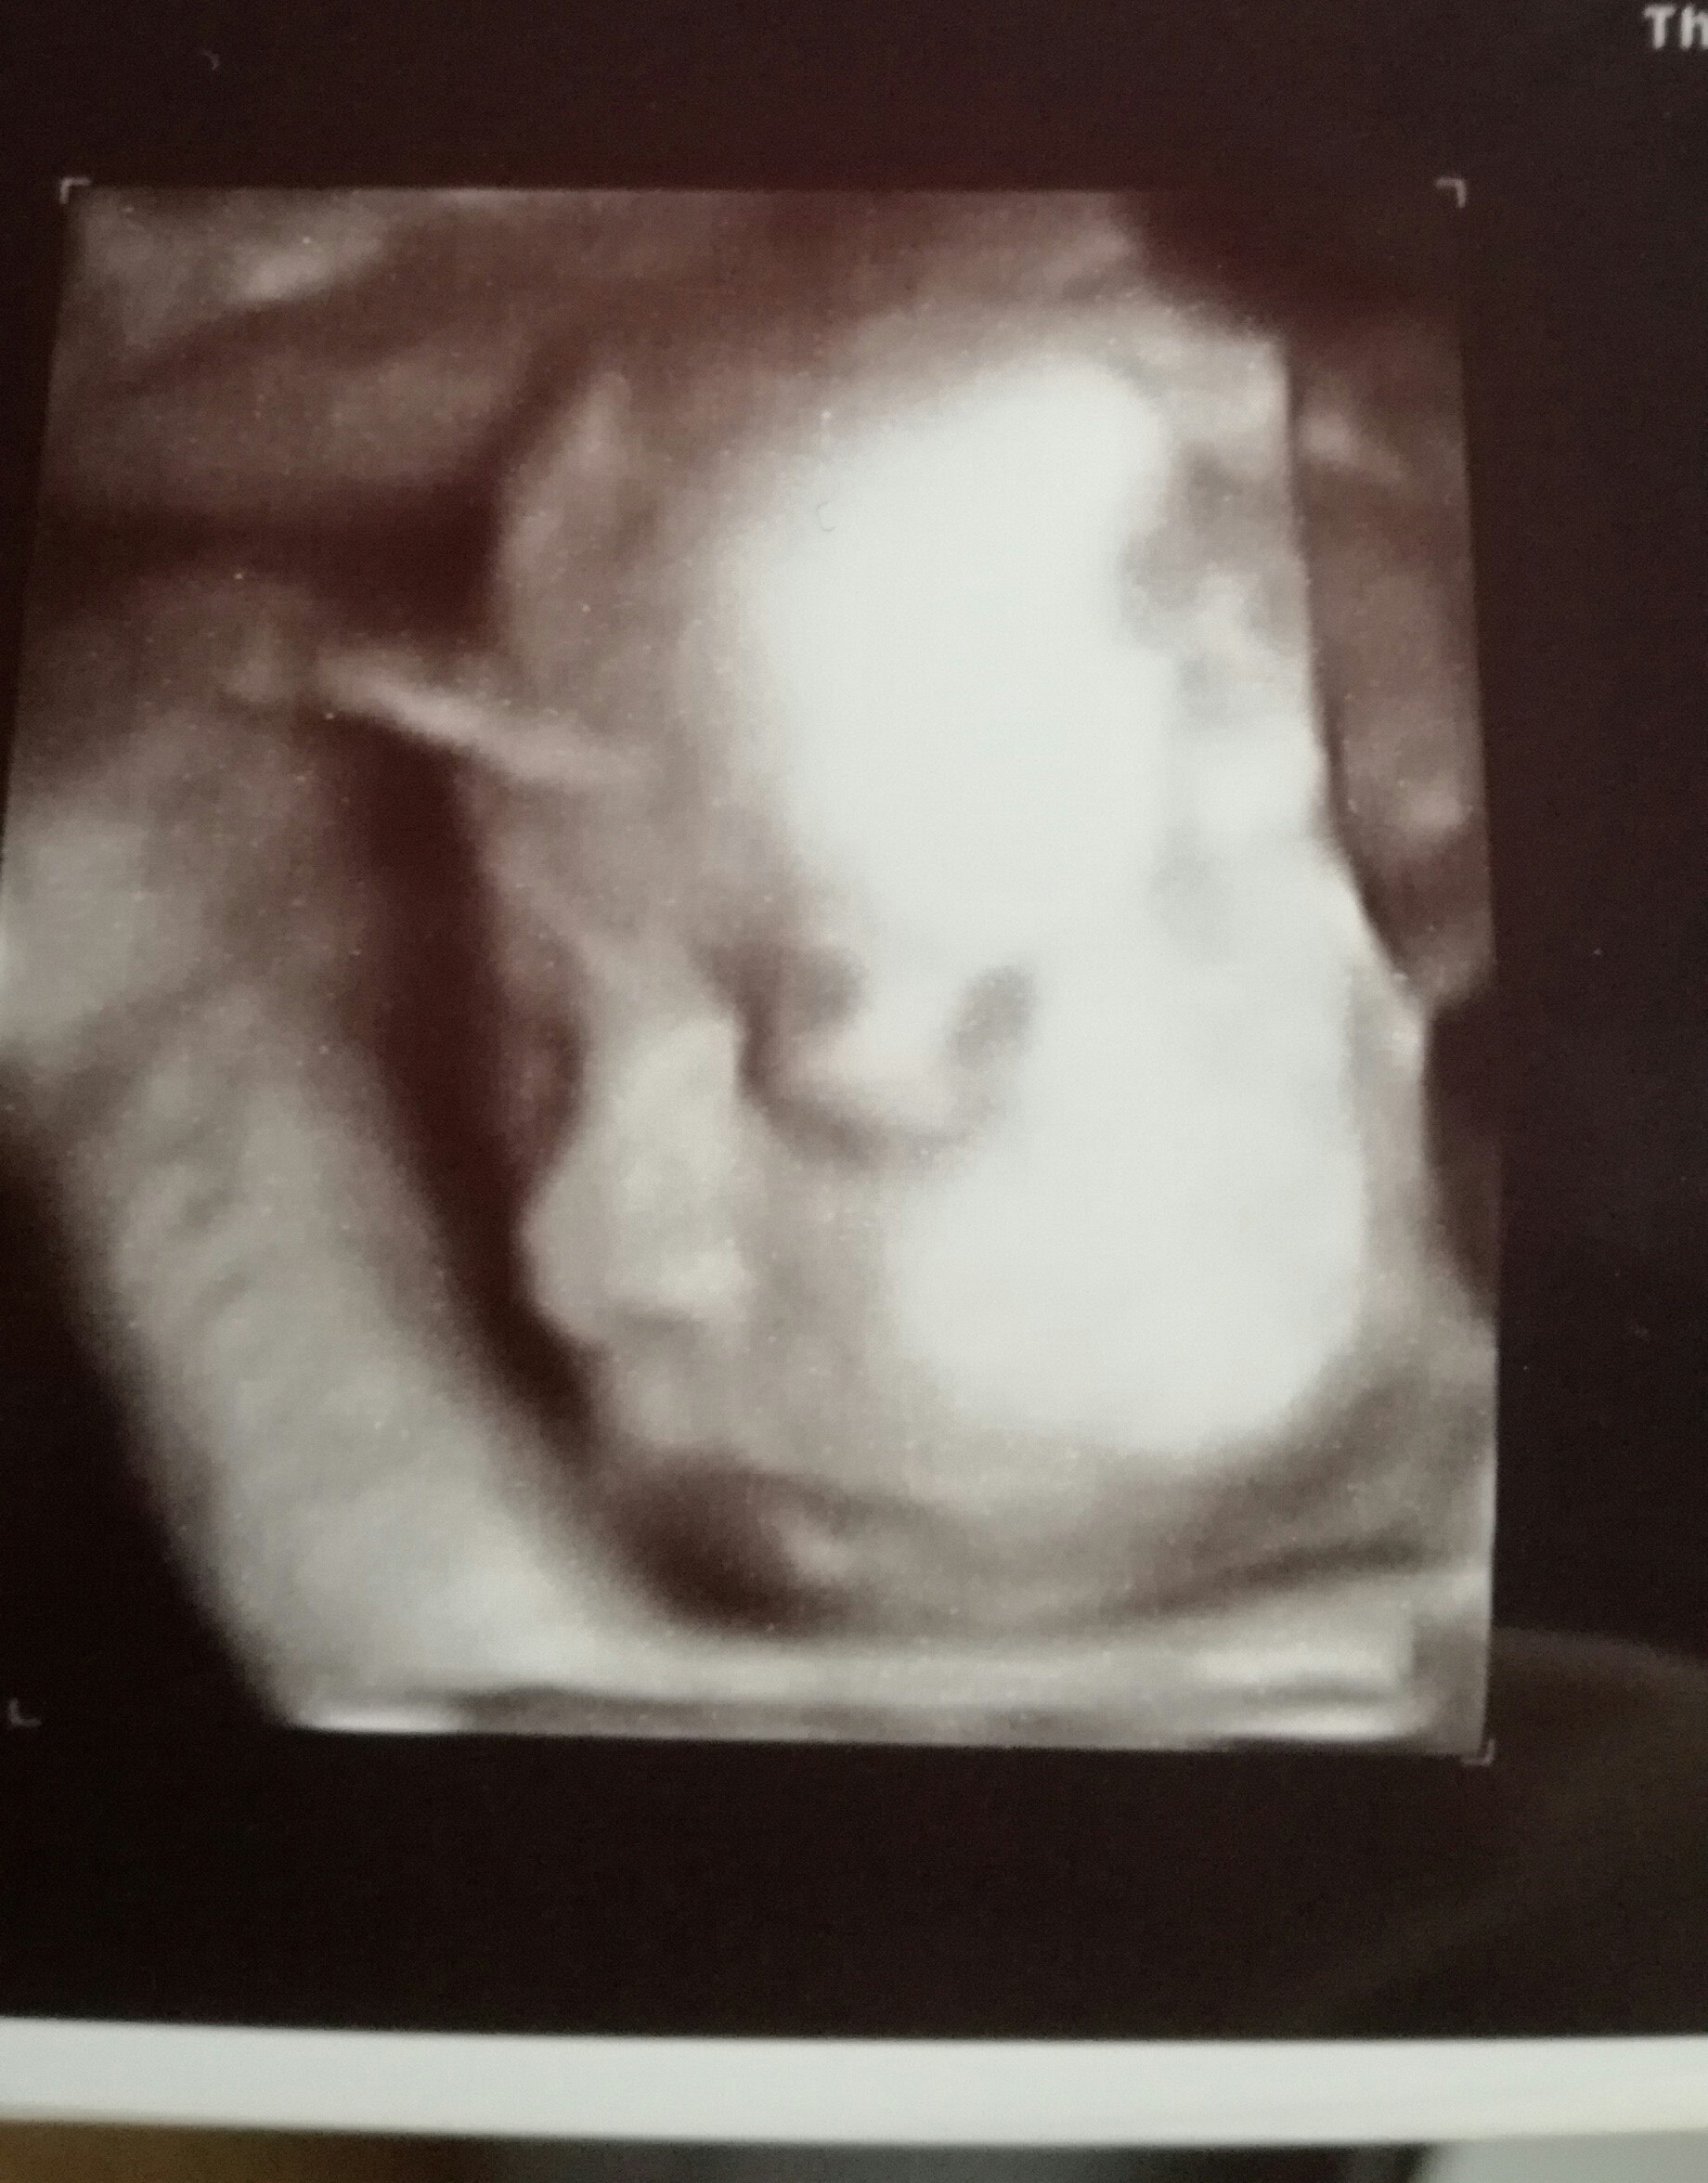

Ja dziś byłam na szybkim 4d :) mała wazy 1.091 kg i chyba bardziej podobna do tatusia póki co ale to wszystko moze się zmienić :) najważniejsze że po mamusi jest od pasa w dół i już nic się w tym względzie nie zmieni ;)

• IMG_20180717_201358-1.jpg

IMG_20180717_201358-1.jpg

666,4 KB · Wyświetleń: 151

• IMG_20180717_201406-1.jpg

IMG_20180717_201406-1.jpg

674,3 KB · Wyświetleń: 150